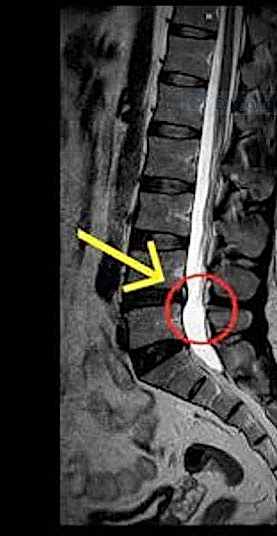

Bel ve boyun fıtığı, omurgadaki disklerin yerinden kayması veya dışarı çıkması sonucu oluşan bir durumdur. Bu diskler, omurlar arasındaki yastıkçıklar olarak görev yapar ve omurga hareketlerini rahatlatır. Ancak, bu disklerin kayması veya patlaması, sinirlere baskı yaparak ağrıya, uyuşma ve kuvvet kaybına neden olabilir.

Bel fıtığı genellikle bel bölgesindeki omurlar arasında meydana gelirken, boyun fıtığı ise boyun omurları arasında oluşur. Bu rahatsızlıkların belirtileri arasında sırt, bel ve boyun ağrıları, bacaklarda uyuşma, kollarda güçsüzlük gibi şikayetler yer alır. Eğer patlamış fıtık tedavisi arıyorsanız, Gaziantep bel fıtığı tedavisi ve boyun fıtığı tedavisi için doğru adrestesiniz.